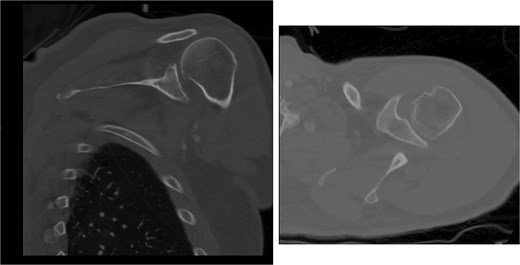

Both shoulders were reduced urgently by the orthopedic team, with immediate improvement in paresthesias (Fig. 2). Post-reduction CTs were significant for bilateral chronic rotator cuff disease with superior migration of the humeral heads, right-sided supraspinatus and subscapularis atrophy, and a left nondisplaced glenoid fracture (Figs 3 and 4). He was discharged home in bilateral slings.

Post-reduction CT of the right shoulder demonstrating superior humeral head migration relative to the glenoid, visualized evidence of prior rotator cuff repair surgery, and a nondisplaced anterior-inferior glenoid fracture.